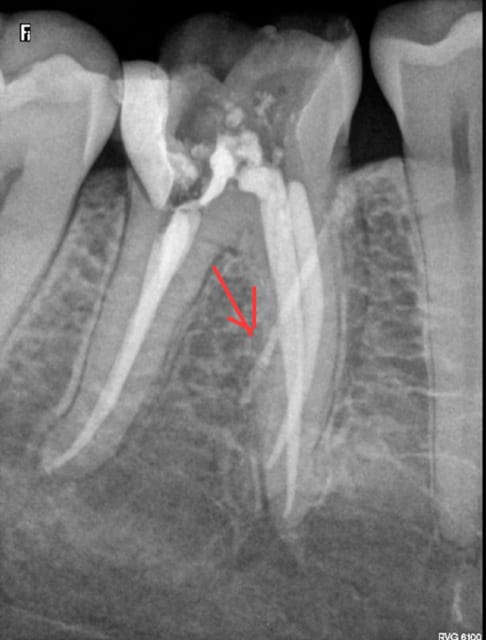

J'ai bien pété une aiguille quick sleeper mais je l'ai enlevée avant . Vous croyez que cette merde a traversé la racine ? C'est curieux quand meme j'ai piqué dans l'espace interdentaire et pas avec une angulation mésio distale. -)

Putain après réflexion je ne vois que ca ! je me disais que la corticale était un peu dure. -)

Une trainée de pâte endo/morceau de gutta sur le capteur radio?

Cette patiente aurait elle subit une anesthésie récente pour cette dent ? Auquel cas il resterait une lésion correepondant au trajet d'une aigueille..

La légère radio opacité de cette image curieuse ne m'inquiète pas du tout.

Ton hypothèse sur le quicksleeper me semble la plus plausible. A faire suivre aux formateurs c'est certes exceptionnelle, mais visiblement ça peut arriver. En tout cas si c'est ça, ca perce bien ce machin là.

percer une racine ca me semble difficile quand même. Mais c'est vrai que l'image ne m'évoque qu'une fuite de pâte dans le trajet de l'aiguille. serais tu juste tangent et a cote d'un canal secondaire?